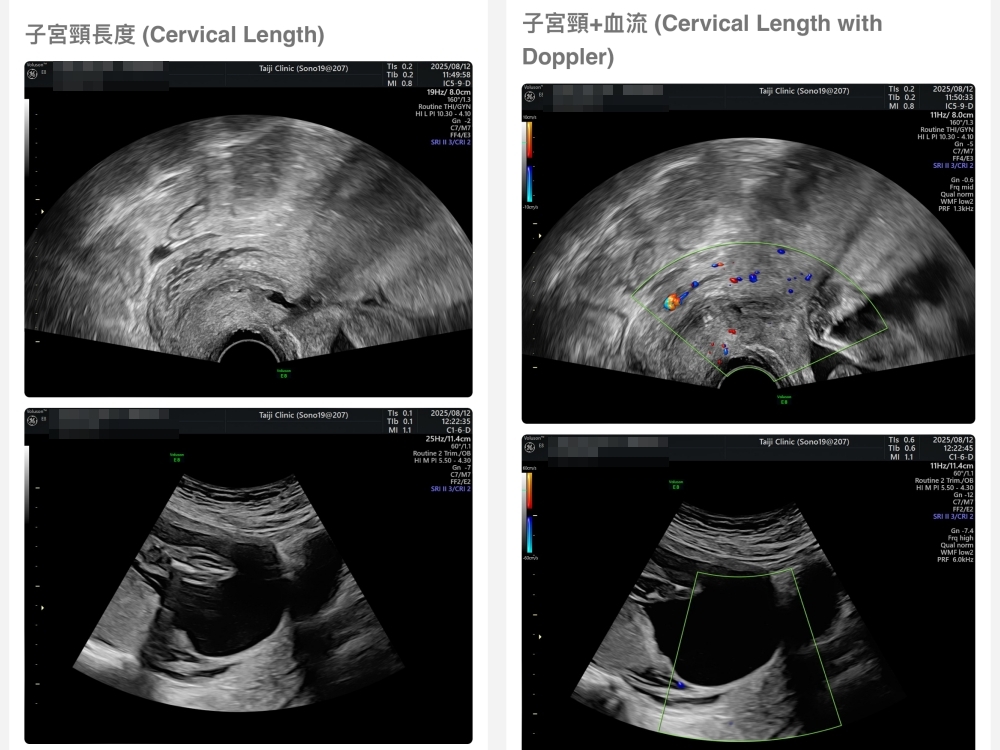

等到11:50進入診間檢查,先照了陰道超音波,確認子宮頸的長度,再照腹部超音波,11:55照完以後會再請家人進到診間內陪同!

▲離開診所後會收到MAIL,我們14:05離開,大約是16:45收到mail,裡面會有滿滿的超音波照片,紀錄的很詳細!也會提供紙本的報告,可以給日後產檢的醫師做參考👌